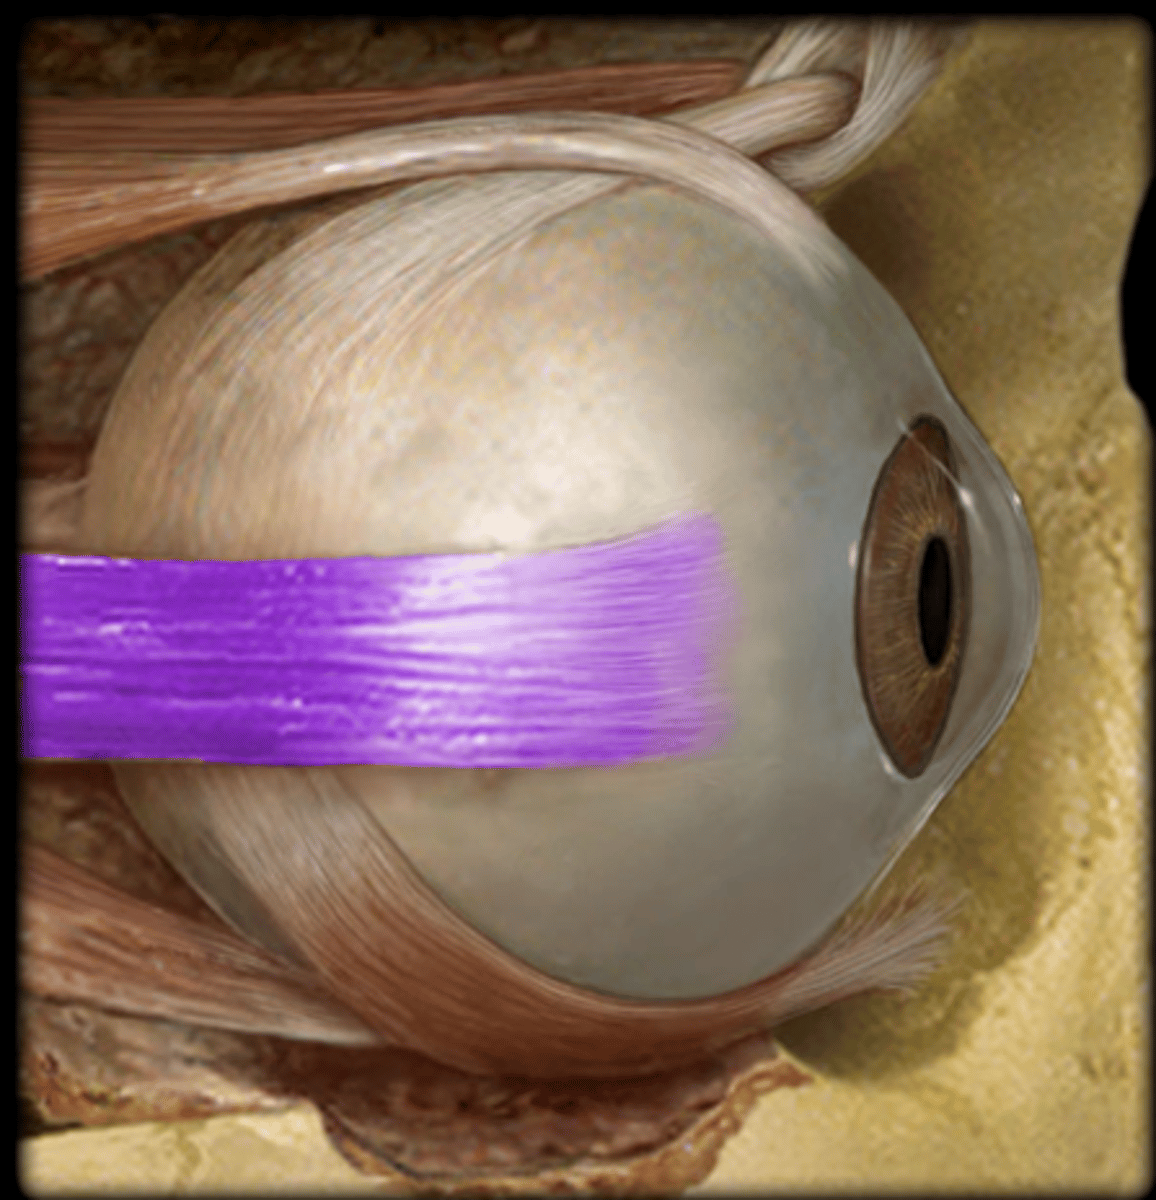

inferior oblique muscle/tendon

inferior rectus muscle

lateral rectus muscle

medial rectus muscle

superior rectus muscle

superior oblique muscle/tendon

medial rectus muscles

inferior oblique muscles or inferior oblique tendon

superior oblique muscle or superior oblique tendon